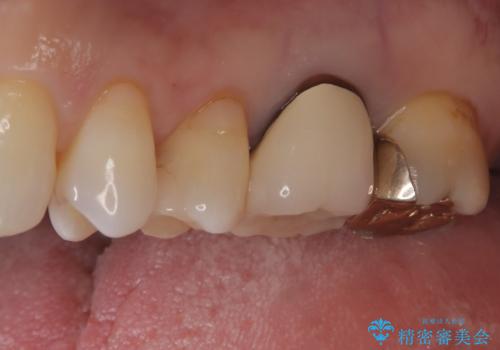

- 奥歯の被せ物が欠けたを主訴に来院された患者様です。欠けてしまった被せ物を除去後セラミックインレーで治療を行いました。

欠けた範囲が大きく被せ物を外して後、セラミックインレーで治療を行いました。欠けたままの状態を放置しているとそこに食べ物が詰まり虫歯になってしまうので早めの治療が必要です。